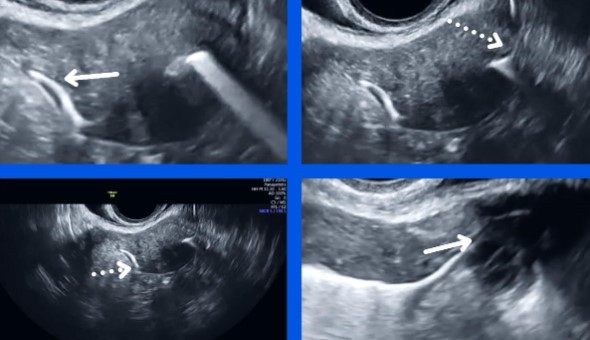

ΥΠΕΡΗΧΟΓΡΑΦΙΚΗ ΣΑΛΠΙΓΓΟΓΡΑΦΙΑ (HYFOSY)

| Η μέθοδος HYFOSY αποτελεί ανώδυνο και ασφαλές εργαλείο για έλεγχο διαπερατότητας σαλπίγγων, απαραίτητο στη διερεύνηση υπογονιμότητας. |

Η εξέταση γίνεται με υπερηχογράφημα, χωρίς ακτινοβολία, και δίνει άμεσα αποτελέσματα, φιλικά για την ασθενή.